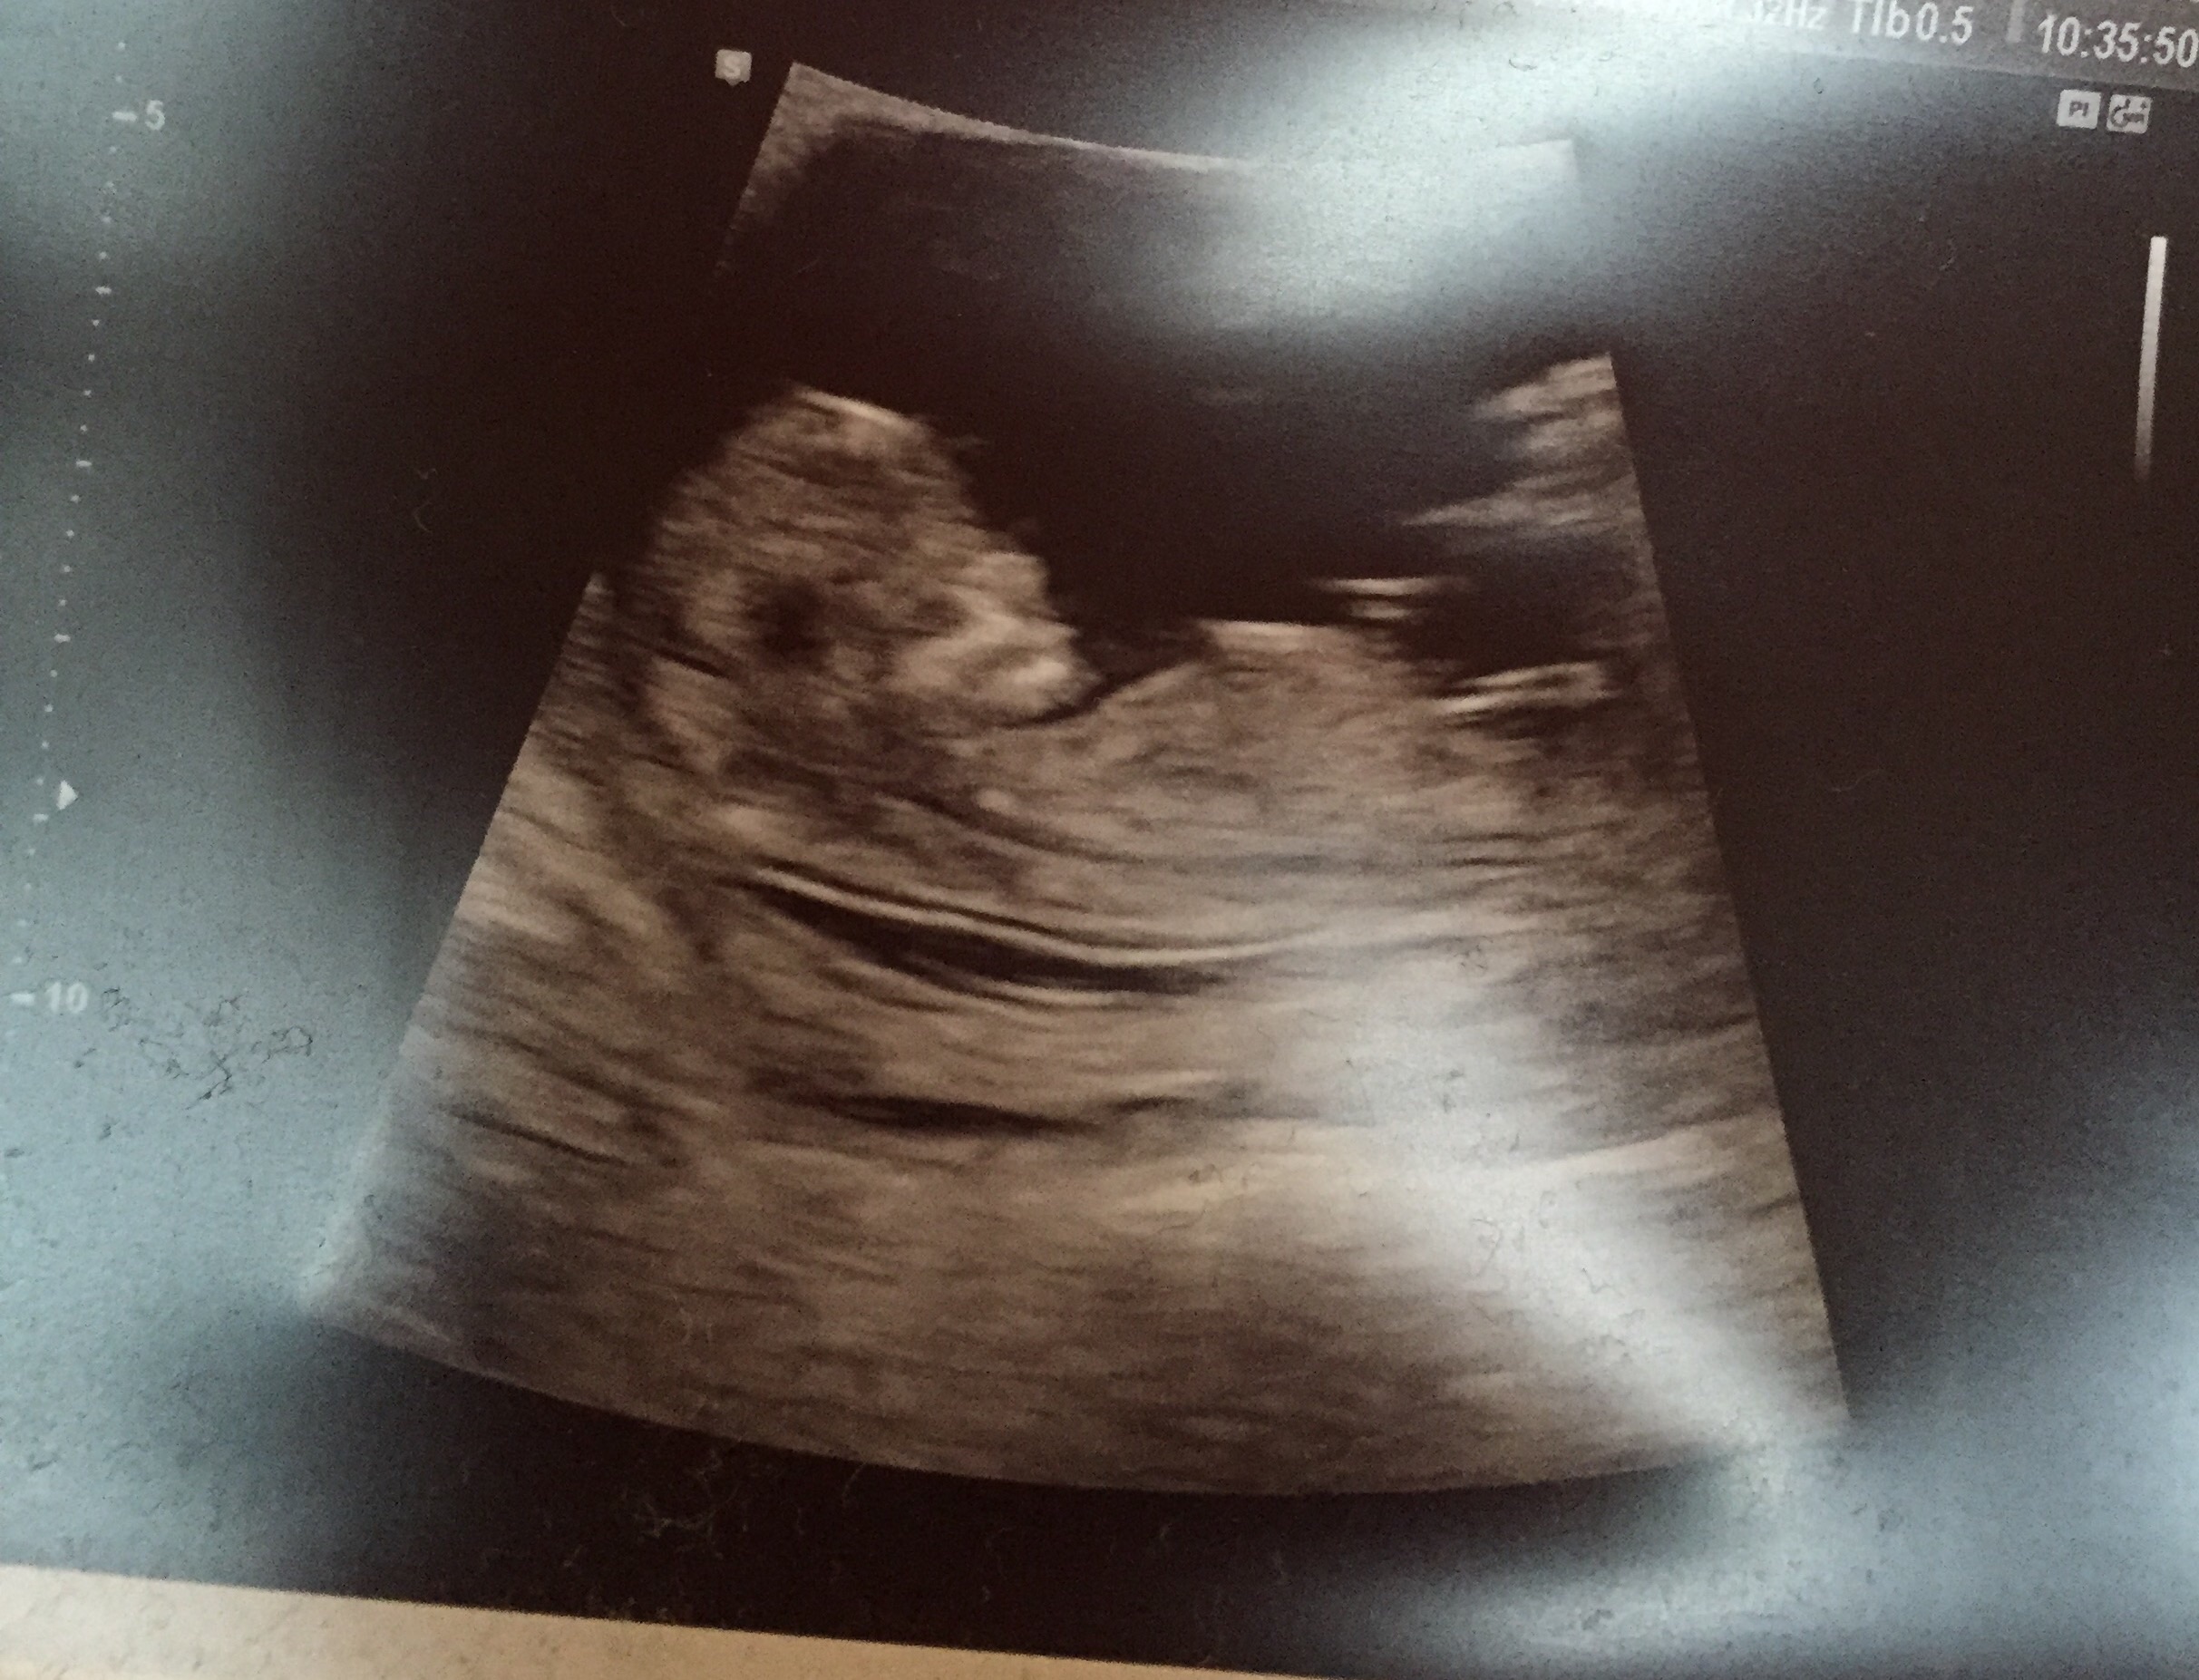

Had my second sonogram today! 12+4 and he/she was moving around like crazy. At first it was laying on its side, so they told me to cough a couple times and doing that made it move onto its back. It's a neat trick they said works every time.

12+4 and he/she was moving around like crazy.

At first it was laying on its side, so they told me to cough a couple times and doing that made it move onto its back. It's a neat trick they said works every time.

(The tech said it's my Halloween baby-skeleton face!).